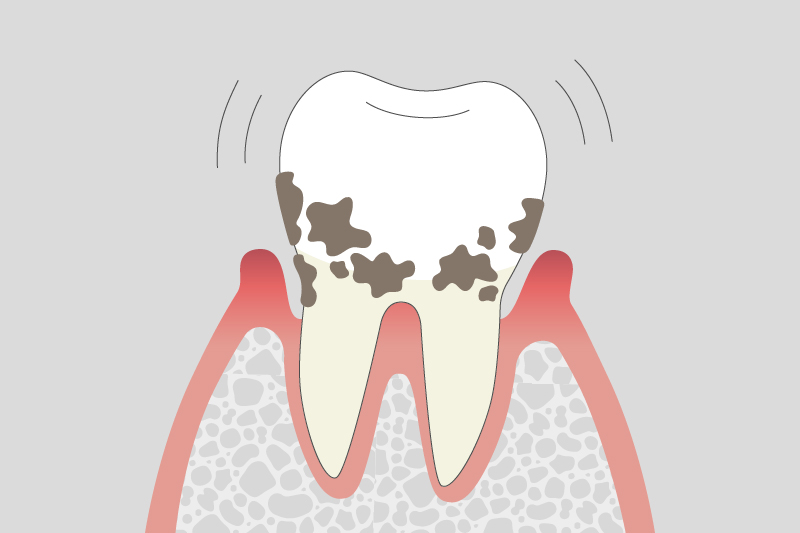

重度歯周炎

歯を支える骨が大幅に失われ、最終的に歯が抜ける可能性が高い。